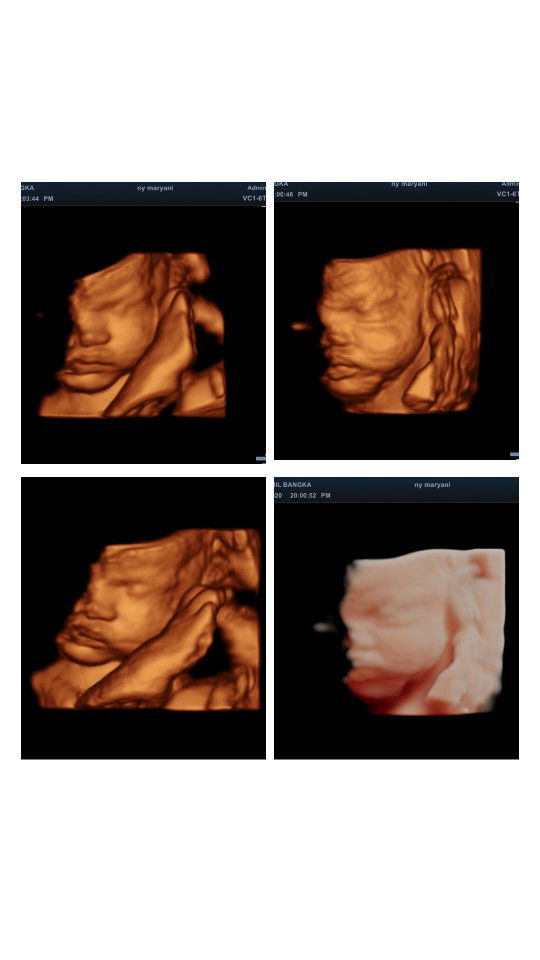

Kalo diusg gapernah ngeliatin muka semuanya selalu setengah? Alhamdulillah baby boy, posisi udah pas masuk panggul. Gimana bunda yang hpl nya april? Semoga sehat selalu dan dipermudah persalinannya ya bun?